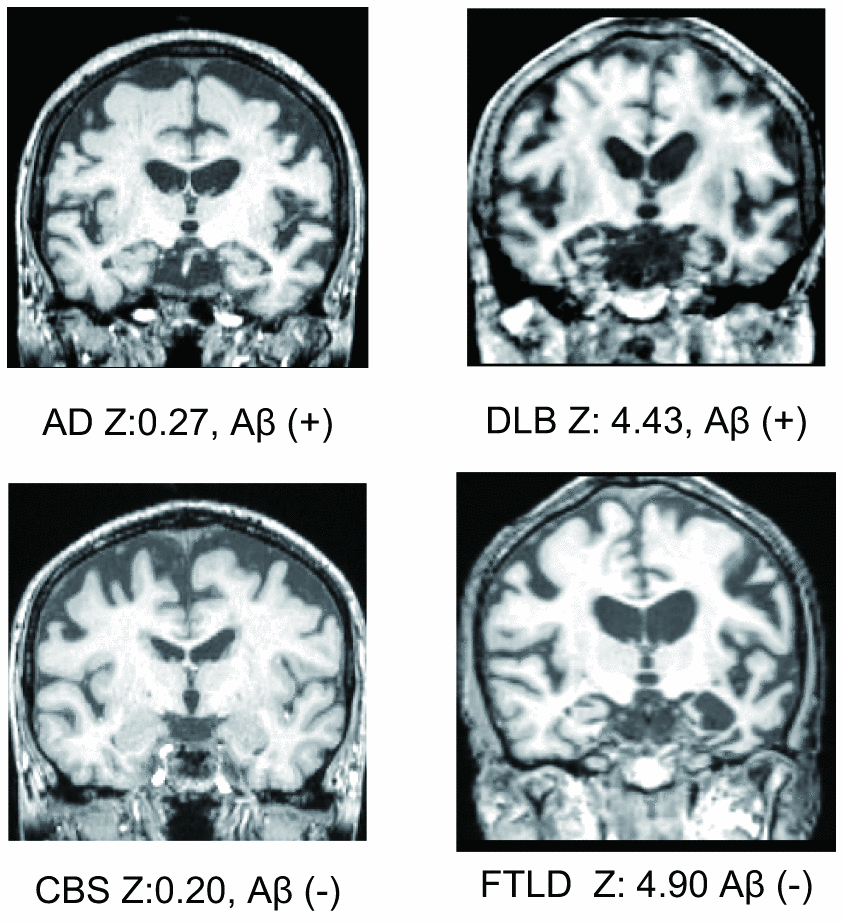

Although a previous study showed that MTL atrophy scores calculated using VSRAD ® Advance have a high sensitivity (86.4%) and a high specificity (97.5%) [2], there are two serious limitations of the study, which impede its reliability in an actual clinical setting. First, the study population included only AD and cognitively normal subjects. In reality, however, clinicians must be able to differentiate between the different types of cognitive disorders such as dementia with Lewy bodies (DLB), fronto-temporal lobe dementia (FTLD), progressive supranuclear palsy (PSP), cortico-basal degeneration (CBD), neurofibrillary tangle-predominant dementia (NFTD), and argyrophilic grain dementia (AGD). Representative MTL images are shown in Figure 1. A previous study showed that only 34% of patients with neurodegenerative dementia (clinical dementia rating scale; CDR ≥ 1) had AD pathology [18] and another showed that there was no significant difference in MTL atrophy between subjects with AD and non-AD dementia [17]. Therefore, while VSRAD ® Advance may be useful for differentiating AD from cognitive normal subjects, the score alone is not sufficient to diagnose AD. Second, the patients assigned to the AD arm of the study were diagnosed based on clinical criteria. However, false positive diagnosis of AD is possible when using clinical criteria alone and similarly, patients with AD pathologies are often misdiagnosed with normal cognition [19]. A paper reviewing the reliability and validity of NINDS-ARDA Alzheimer’s criteria [20] found that the sensitivity and specificity of the ‘probable AD’ category was 76.6 – 70.9% and 59.5 – 70.8%, respectively; and those of the ‘probable AD’ and ‘possible AD’ categories combined were 87.3 – 82.7% and 44.3 – 54.5%, respectively [21]. Lim et al. [22] also showed that the ‘probable AD’ category had 83% sensitivity and 55% specificity; ‘probable AD’ and ‘possible AD’ categories combined had 85% sensitivity and 50% specificity. In a population-based study by Petrovitch et al. [23], only 65% of the clinically diagnosed AD was reported to be pathologically accurate. Amyloid imaging is reported to alter the presumptive diagnosis in approximately 30% of cases, increase the diagnostic confidence in about 60% of cases, and change the patient management in about 60% of cases [24]. Owing to the high reliability of amyloid positron emission tomography (PET), a positive result can be considered as a clear confirmation of AD pathology.

Figure 1. Representative medial temporal lobe images, VSRAD Z scores, and amyloid positivity.